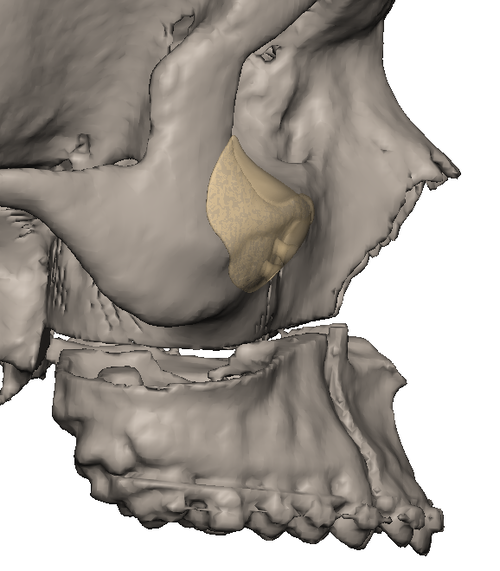

im getting surgery(trimax and infras) soon, any thoughts on this?my left side (the 31 mm) is also less wide in real life, i think would be good to extend it more to the nose area.